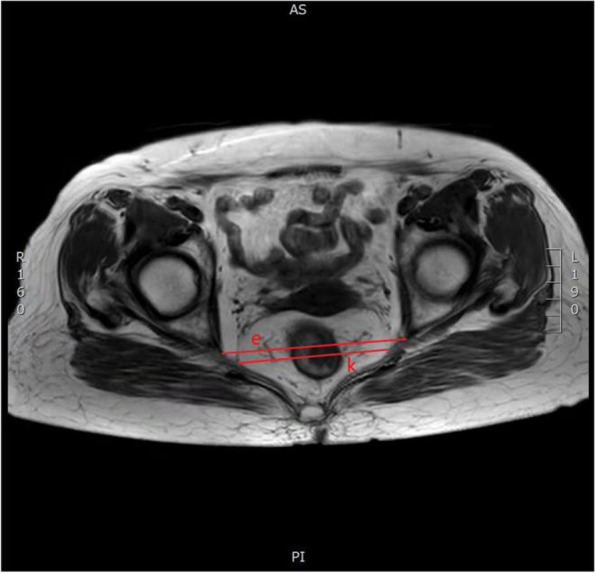

Fig. 3.

Horizontal pelvic magnetic resonance images: e pelvic outlet transverse diameter and k mesorectal fat area

| (e) Pelvic outlet diameter | The line between the sciatic spines on both sides (Fig. 3) | [6, 15, 20, 22–29] |

| (k) Mesorectal fat area | The area of mesangium and fat around the rectum at the level of the tip of the sciatic spine (Fig. 3) | [13, 23, 25, 26] |